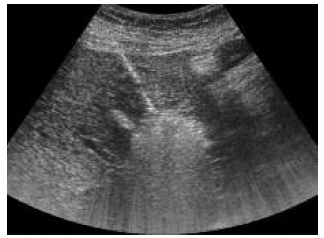

One such combined strategy is the combination of radiofrequency ablation and transarterial chemoembolization. A combination of transarterial chemoembolization followed by radiofrequency ablation has been used to minimize heat loss because of perfusion-mediated tissue cooling and to increase the therapeutic effect of radiofrequency ablation (Figures 5-9).26 Radiofrequency ablation and transarterial chemoembolization are more effective for complete tumor necrosis rate in patients with hepatocellular carcinoma.21,27 Local tumor progression rate was significantly lower in the transarterial chemoembolization and radiofrequency ablation-treated group than in the radiofrequency only ablation group (6%-39%).28

Figure 7 and 8. Ultrasonography Visualization of Hepatocellular Carcinoma Nodule Before and After Selective Chemoembolization